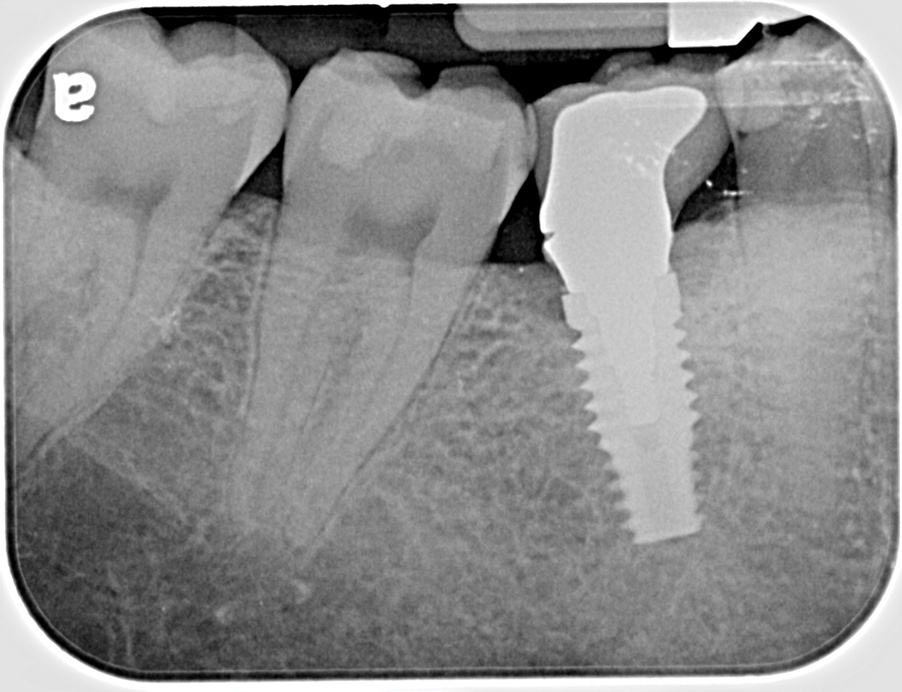

Fig 16. Radiograph depicting closed contact at time of implant insertion.

Figure 16

Fig 17. Open proximal contact between implant and adjacent tooth 3 years post insertion.

Figure 17

During the initial planning phase for implant therapy, the dental practitioner should not assume that the existing position of the teeth within the dental alveolus will remain stationary throughout the patient’s lifetime. Long-term follow-up of implant restorations has proven that often it does not remain stationary, regardless of the age of the patient. Open contacts have frequently been reported between implants and adjacent teeth.30

Open proximal contacts between implants and adjacent teeth have been attributed to ongoing craniofacial growth31 and vector forces mesializing tooth position (Figure 16 and Figure 17).32 These changes, particularly in the esthetic zone, can contribute to differences in incisal edge position, gingival margin height, and the facial contour and alignment of the dental arch (Figure 18 and Figure 19).31 Jemt et al30 studied a population of 28 consecutive anterior implant crowns followed for 15 years. During this time, only 8 patients demonstrated no movement of the adjacent teeth; 55% of adjacent teeth displayed palatal tooth movement, predominately in the female population.30 Shifting of teeth can contribute to occlusal changes leading to uneven occlusal load and distribution among the arch.31 Similar to adjacent open contacts between teeth, any open contact can lead to food impaction/accumulation, pocketing, and inflammation of the interdental tissue.